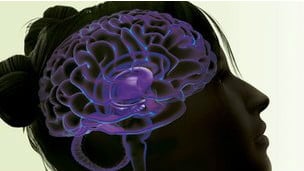

Durante mucho tiempo se ha sabido que los cerebros de los adictos a drogas presentan diferencias, pero no se sabía si esas diferencias eran resultado del abuso de sustancias o existían previamente.

Durante mucho tiempo se ha sabido que los cerebros de los adictos a drogas presentan diferencias, pero no se sabía si esas diferencias eran resultado del abuso de sustancias o existían previamente.

El nuevo estudio, financiado por el Consejo de Investigación Médica (MRC) del Reino Unido, intentó responder a esa pregunta comparando los cerebros de 50 adictos a cocaína o crack con el cerebro de sus hermanos no adictos, que nunca habían utilizado las sustancias.

Encontraron que tanto los adictos como los hermanos no adictos tenían las mismas anormalidades en la región del cerebro que controla la conducta, los circuitos frontoestriatal.